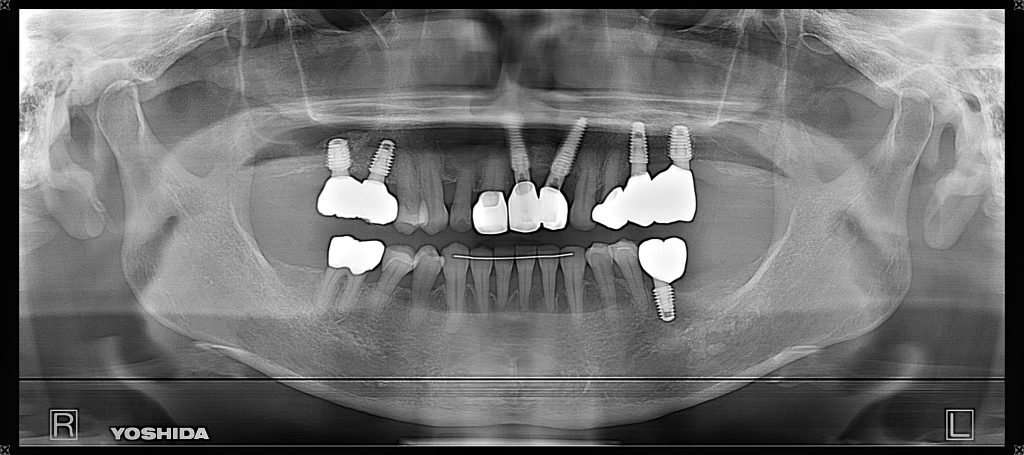

症例250代 男性 歯根破折にて右上5番を抜歯

治療後

ブリッジ・義歯・インプラントの選択肢を提案。

力学的に強く、両隣在歯に負担のかからないインプラントを選択。

ソケットリフト(上顎洞洞底膜挙上術)を行い、骨の高さを確保しインプラントを埋入。

オペ後、骨との密着値も良く、約3ヶ月後にはジルコニアを装着し終了。

リスクとしては外科的侵襲がある。デメリットは、保険外診療の為、経済的負担がある。

費用 64万(税込)(オペ・仮歯・最終補綴物まで含む)